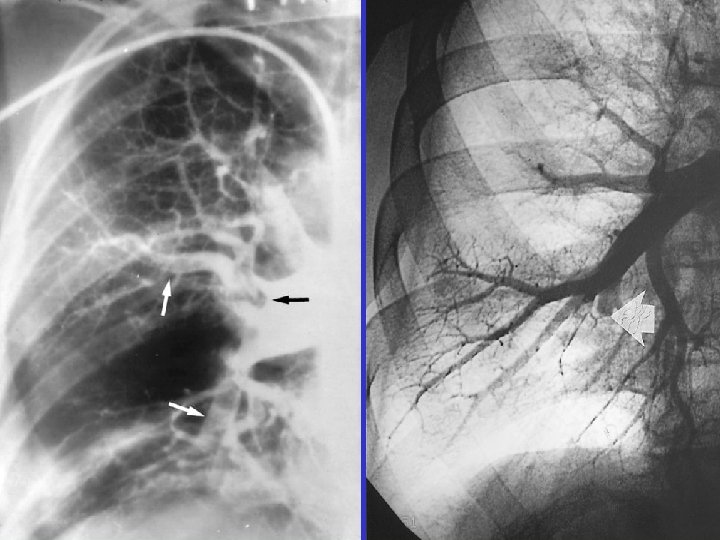

Angiography: massive PE Acute: 45/20 mm. Hg Subacute: 85/50 mm. Hg

CTPH m. PAP = 75 mm. Hg